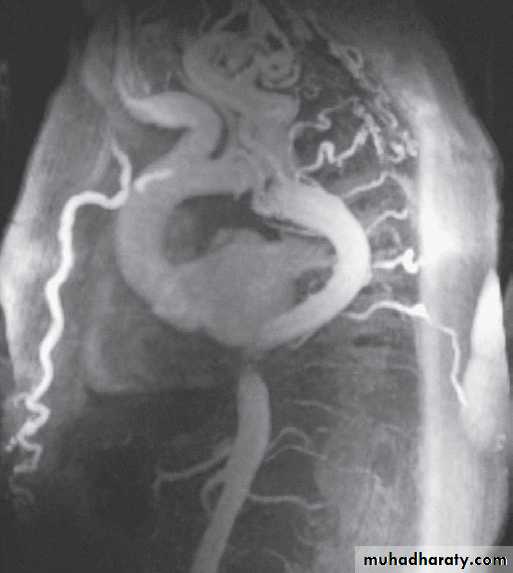

MRI is the best imaging modality